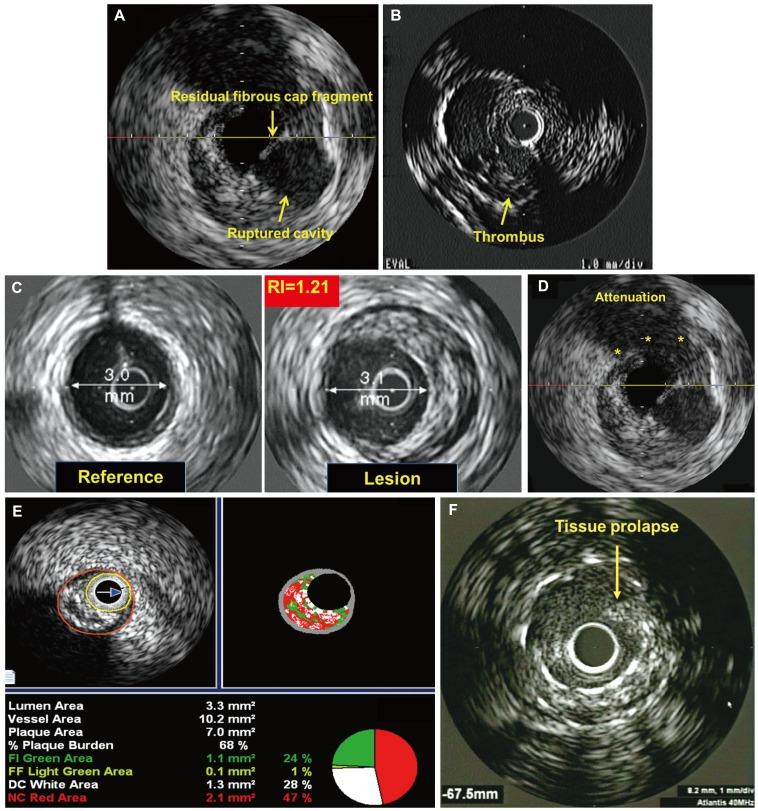

Rupture of a vulnerable plaque and subsequent thrombus formation are important mechanisms leading to the development of an acute myocardial infarction (AMI). Typical intravascular ultrasound (IVUS) features of AMI include plaque rupture, thrombus, positive remodeling, attenuated plaque, spotty calcification, and thin-cap fibroatheroma. No-reflow phenomenon was attributable to the embolization of thrombus and plaque debris that results from mechanical fragmentation of the vulnerable plaque by percutaneous coronary intervention (PCI). Several grayscale IVUS features including plaque rupture, thrombus, positive remodeling, greater plaque burden, decreased post-PCI plaque volume, and tissue prolapse, and virtual histology-IVUS features such as large necrotic corecontaining lesion and thin-cap fibroatheroma were the independent predictors of no-reflow phenomenon in AMI patients. Non-culprit lesions associated with recurrent events were more likely than those not associated with recurrent events to be characterized by a plaque burden of ≥70%, a minimal luminal area of ≤4.0 mm(2), or to be classified as thin-cap fibroatheromas.

易损斑块破裂及随后的血栓形成是导致急性心肌梗死(AMI)发生的重要机制。AMI典型的血管内超声(IVUS)特征包括斑块破裂、血栓、正向重构、斑块衰减、斑点状钙化及薄帽纤维粥样斑块。无复流现象归因于经皮冠状动脉介入治疗(PCI)时易损斑块机械破碎产生的血栓和斑块碎片栓塞。包括斑块破裂、血栓、正向重构、更大的斑块负荷、PCI术后斑块体积减小及组织脱垂等多种灰阶IVUS特征,以及诸如大坏死核心病变和薄帽纤维粥样斑块等虚拟组织学-IVUS特征,是AMI患者无复流现象的独立预测因素。与复发事件相关的非罪犯病变比那些与复发事件无关的病变更有可能具有≥70%的斑块负荷、≤4.0 mm²的最小管腔面积,或被归类为薄帽纤维粥样斑块。